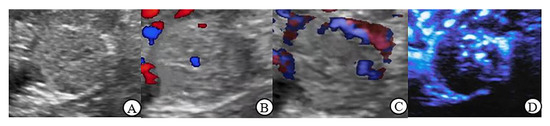

3.4. CDFI, PDI and MFI Evaluation of Blood Flow Characteristics in Benign and Malignant Renal Tumors > 4 cm

3.5. Peripheral Blood Flow Characteristics of Renal Tumor in MFI Mode